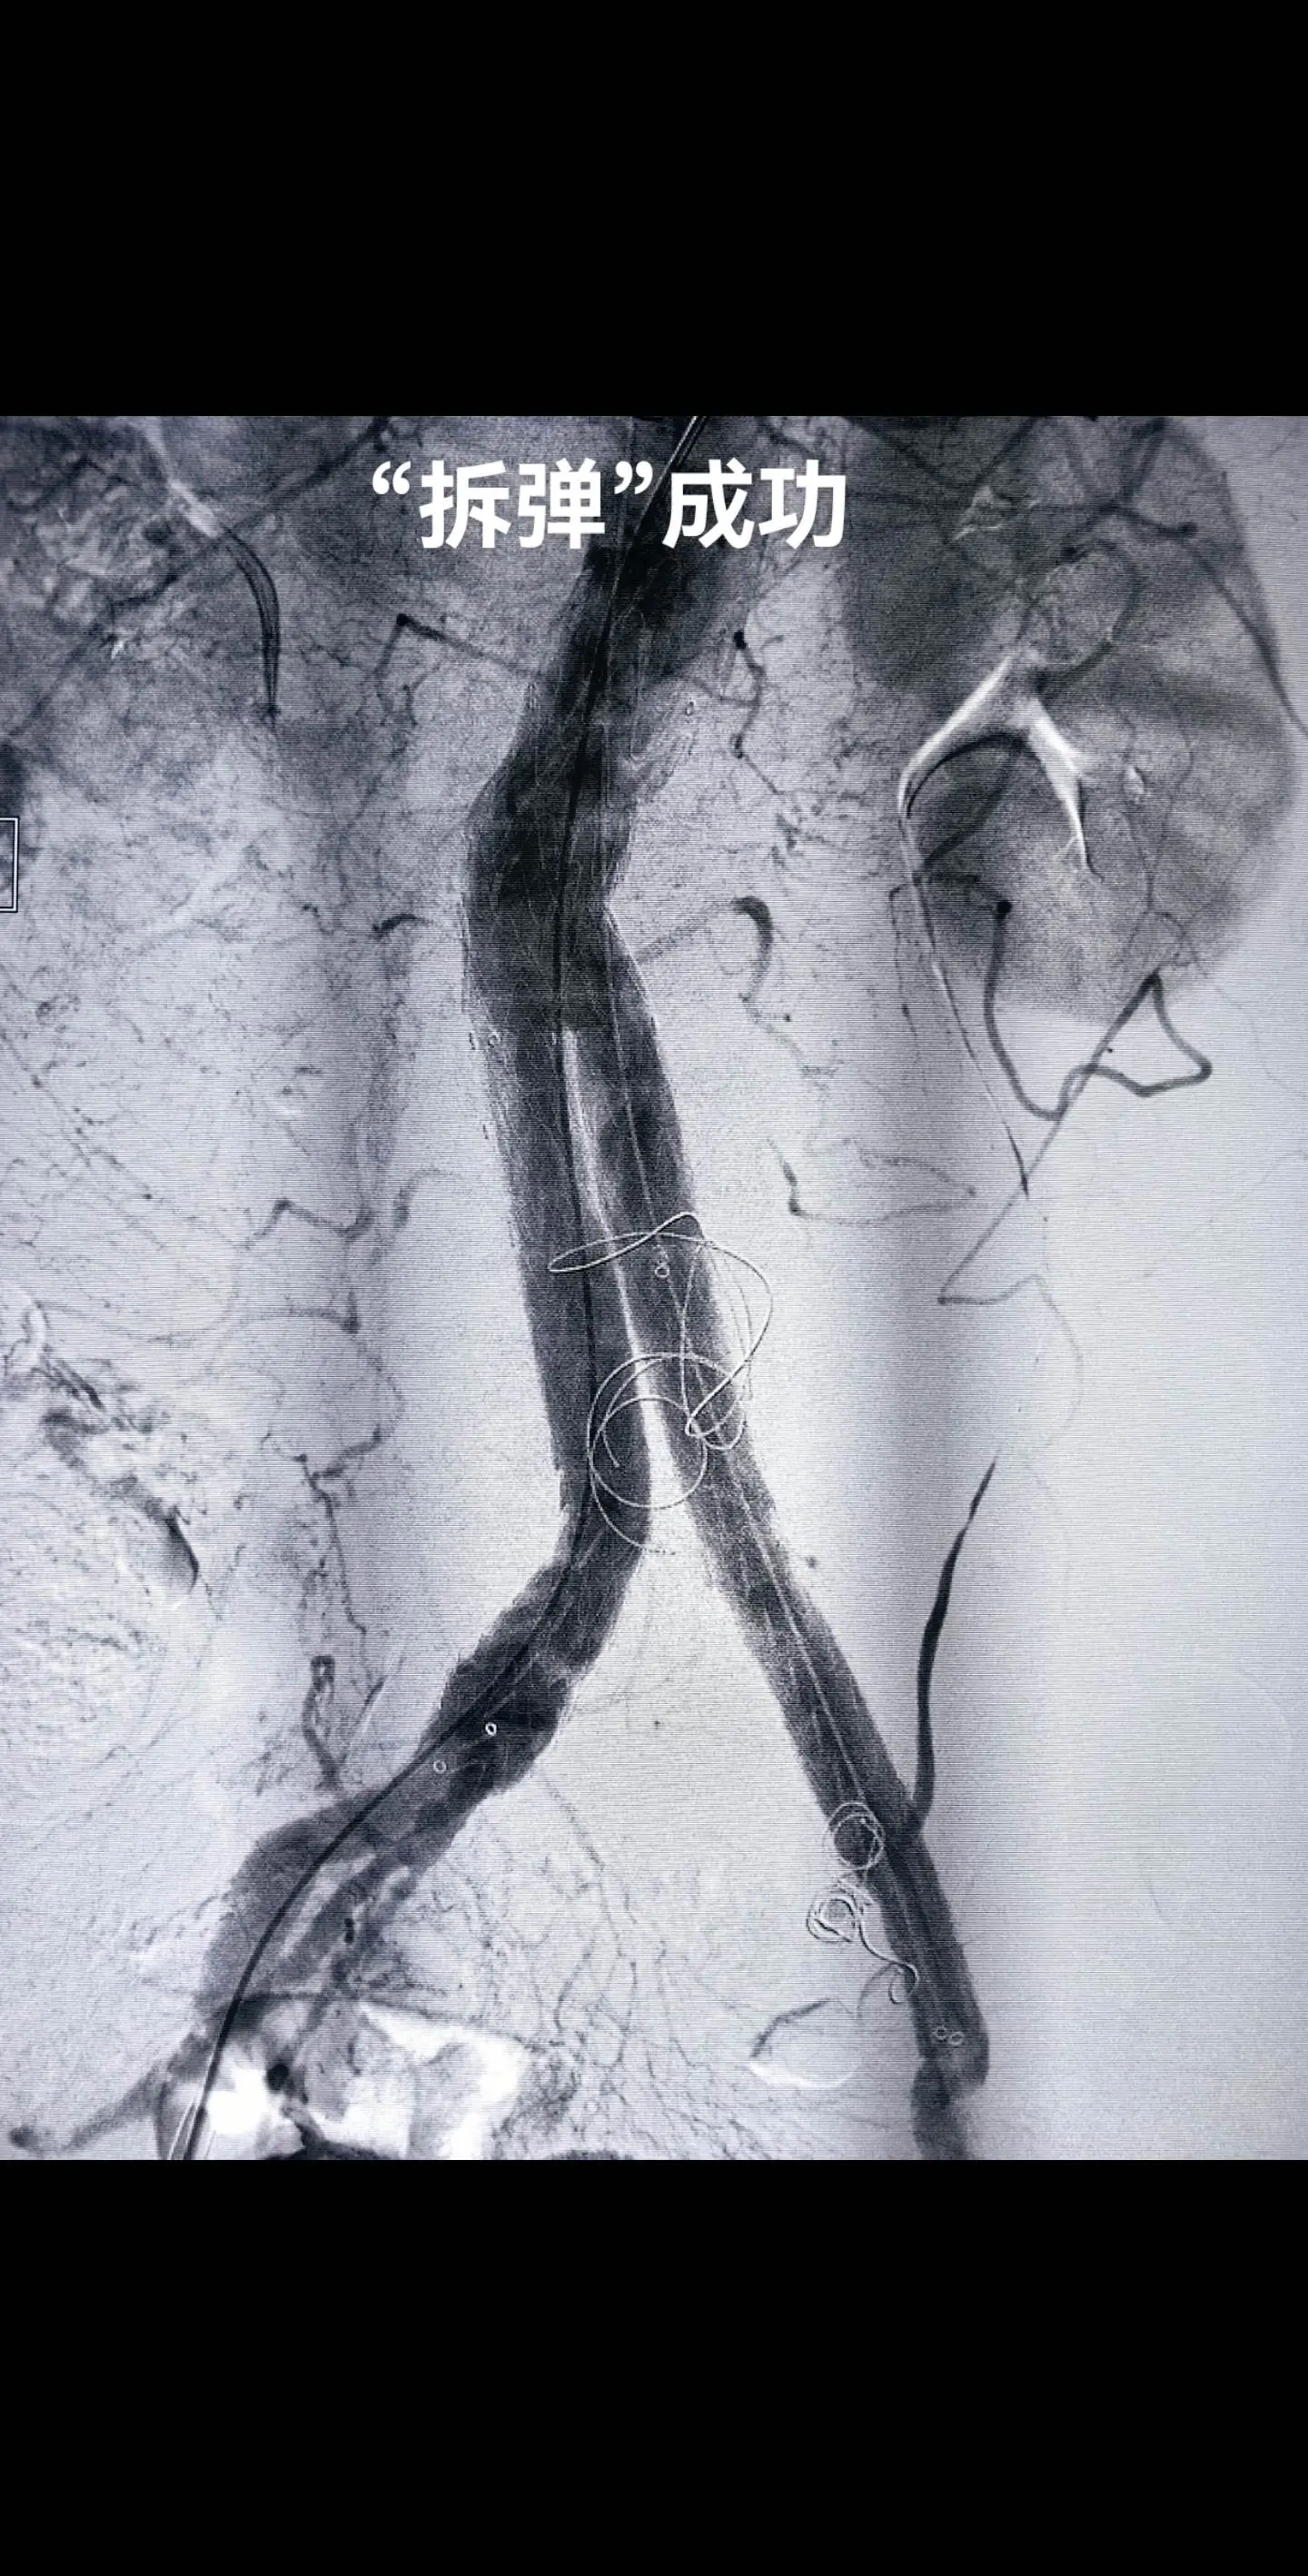

为血透患者维护生命线